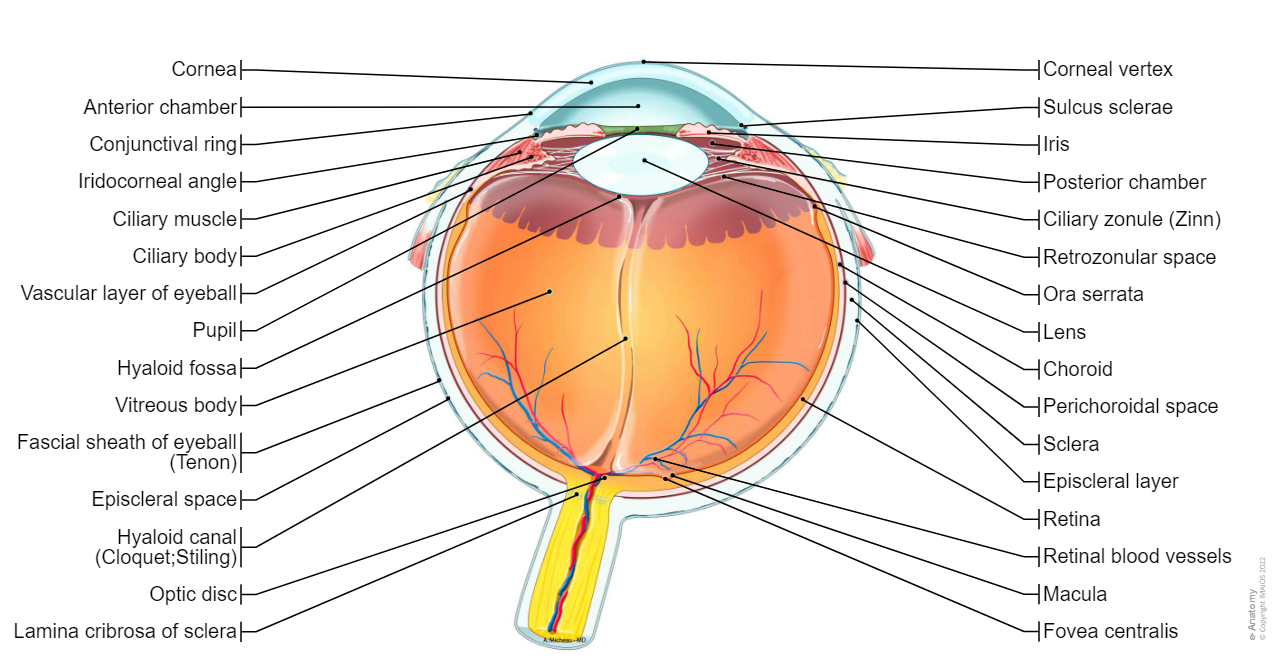

Eyeball/Eye - General Anatomy: Anterior chamber, Iridocorneal angle, Posterior chamber, Vitreous body, Cornea

Eyeball/Eye : General Anatomy